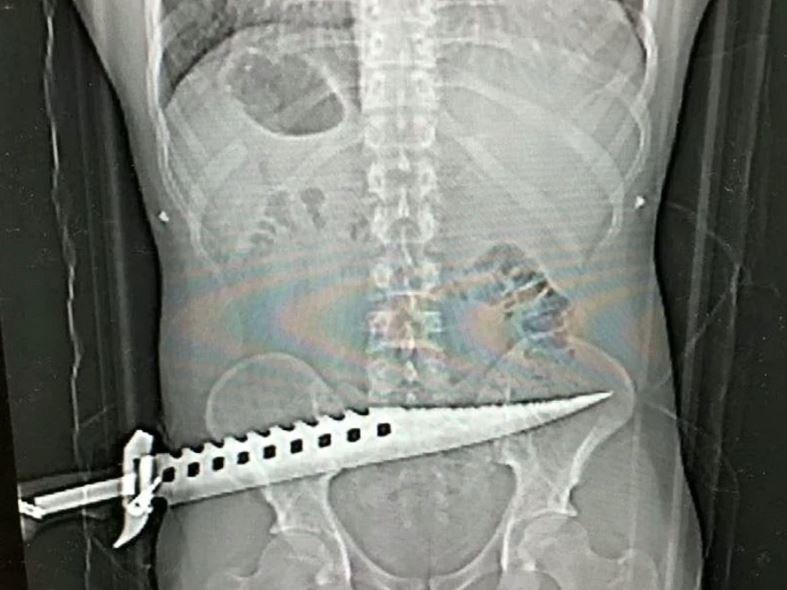

İntikam almak için saldıran Parker, dev boyutlardaki bir bıçağı adamın kalçasına sapladı. Parfitt'in hoşlandığı kadınla birlikte olan kurban olay yerinde güçlükle kaçabildi. Ambulansı arayan talihsiz adam hastaneye kaldırıldı. Hastaneye gidince doktorlar şaşkına döndü. Zira adamın kalçasında avcılıkla ilgilenenlerin kullandığı ve "zombi bıçağı" olarak da bilinen keskin ve uzun bir bıçak duruyordu.

Röntgen ve tahliller yapıldıktan sonra adam ameliyata alındı. Saldırganlar kısa bir süre içerisinde yakalanırken hastanın sağlık durumunun iyi olduğu açıklandı. Davayı inceleyen dedektif Scott Anger, "Bu çok korkunç ve ciddi bir saldırı. Neyse ki saldırıda kimse hayatını kaybetmedi. Hastanın sağlık durumunun iyi olması bizi rahatlattı. Saldırganları da yakaladık" dedi.